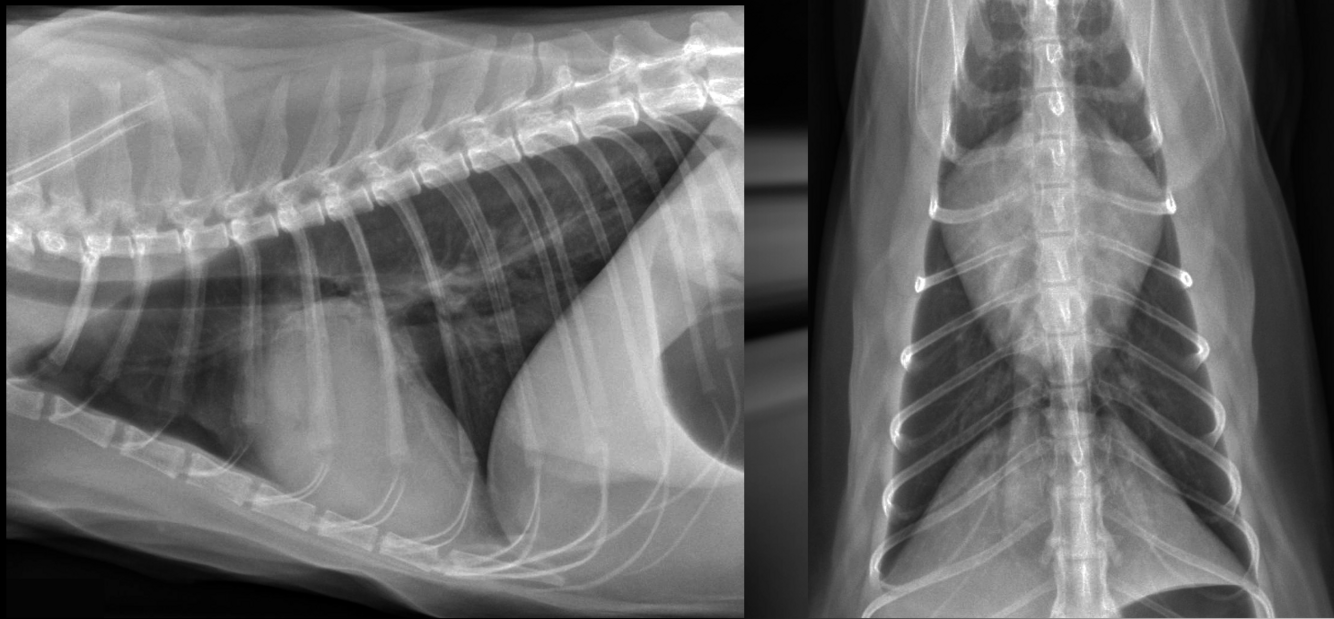

What is shown in these images?

A

pulmonic stenosis

-right heart enlargement

-main pulmonary artery segment enlargement

-possible right heart failure